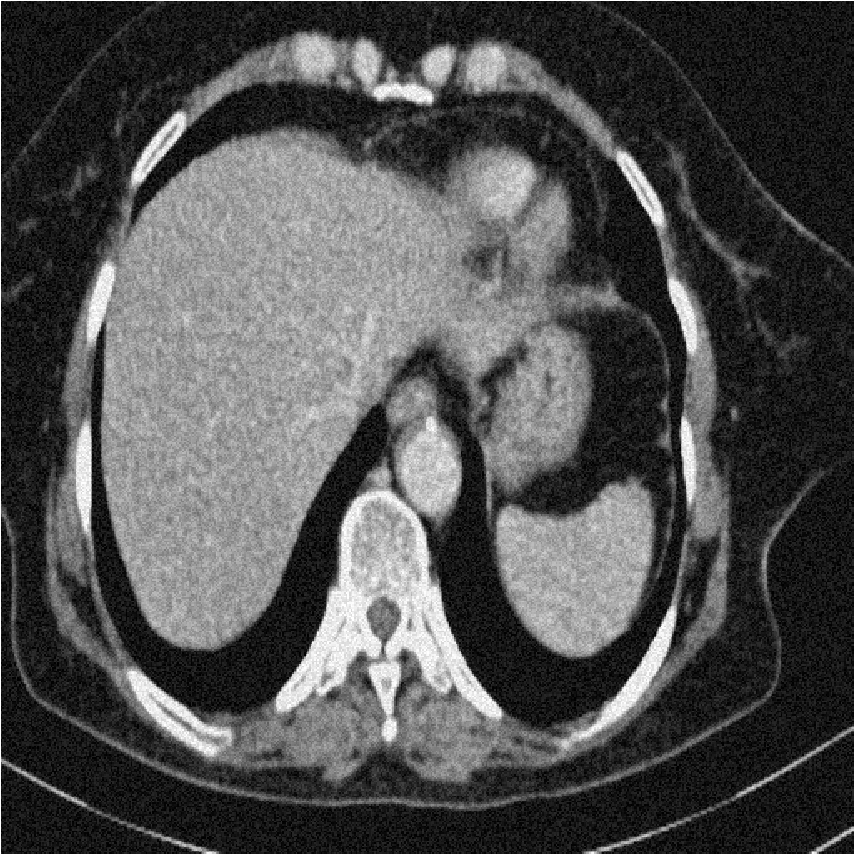

We performed extensive numerical simulations to examine the performance of the aforementioned denoising methods. For this purpose, we used a pixel grayscale CT scan image, shown in Fig. 2a. Noisy versions of this image were created by adding different types of noise at various strengths. The noise types considered are Gaussian noise, uniform noise, salt and pepper noise, and Poisson noise. The following subsections present and explore the results obtained from the various denoising methods. All computational programming were carried out using Mathematica 12.0.

[a)Clean]

[b)Gaussian]

[c)Uniform]

[d)Poisson]

[e)Salt Pepper]

This finding highlights a critical principle in image processing: the implementation strategy (global vs. local processing) can be as important as the choice of transform itself. Future work could explore local or adaptive wavelet thresholding schemes (e.g., context modeling, spatially varying thresholds) to leverage the strengths of wavelets while incorporating the local adaptability that made DFCT successful in this study. Figs. 8-11 show visual comparison of denoising results for the four kinds of noise. In the Figs. 8-11 the left image is noisy input image, the middle image is denoised image using the best wavelet method (BIOS wavelet with Hyperbola threshold for case of Gaussian and uniform noise, BIOS wavelet for Poisson noise and Daubechies wavelet with SURELevel for salt-and-pepper noise) and, the right image is denoised using DFCT.